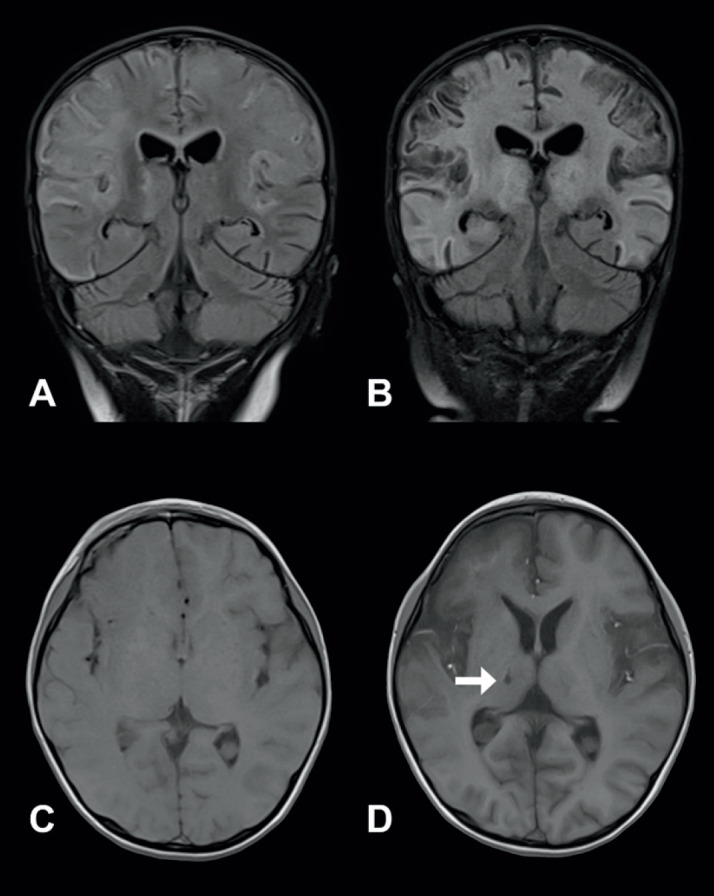

Results: There are 12 children with anti-NMDARE after HSE and 2 children after JE. The median age was 2.1 years (range 0.6-12.9), with 8 male patients. All patients (100%) had fever and seizures, while 50% exhibited focal neurological signs. No patients experienced movement disorders, psychiatric symptoms, or sleep disturbances during the viral encephalitis phase. In contrast, the most common symptoms during the anti-NMDARE phase were as follows: movement disorders in 92.9% (13/14), recurrent or prolonged fever in 71.4% (10/14), sleep disturbances in 64.3% (9/14), seizures in 50% (7/14), and psychiatric symptoms in 50% (7/14). The median cerebrospinal fluid (CSF) white blood cell count in the viral encephalitis and anti-NMDARE phases was 57 (4-410) and 13 (2-48), respectively. The mean CSF protein concentration was 0.43 ± 0.16 g/L and 0.85 ± 0.63 g/L, respectively. Brain MRI was performed in both encephalitis phases for 10/14 patients, with 8/10 showing no new lesions.

Conclusion: There were differences in clinical symptoms and CSF findings between the two phases of encephalitis; however, most patients did not develop new lesions on brain MRI.